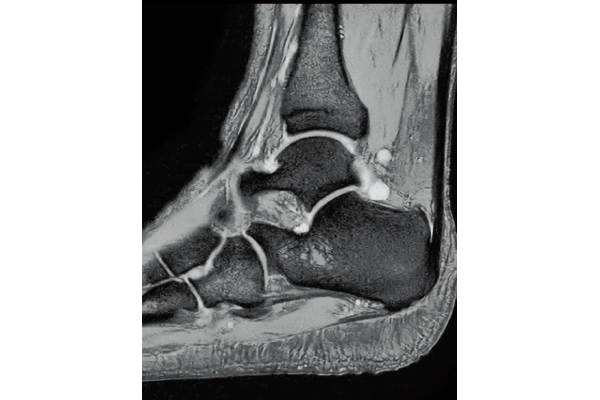

3DisoFSE T2WI

0.75×0.75×1.1(0.55)mm

MPR COR

3D T1WI COR

2.2×1.5×1.5 mm

3st total scan time 0:54